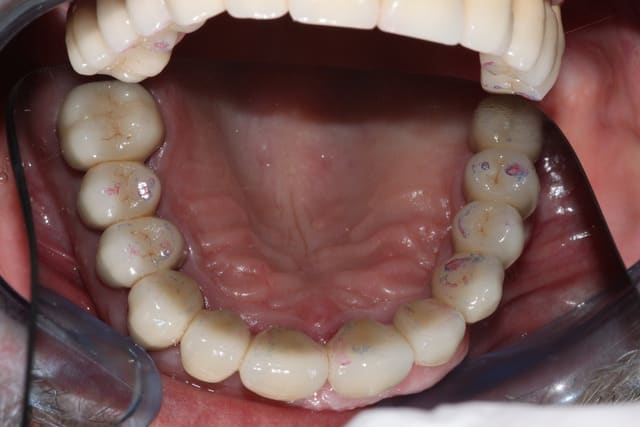

Suite du boulot: le bas

Quelques semaines plus tard, on prépare 37 36 34, ainsi que la 44, conservée vivante. J'ai hésité à aller chercher un ancrage radiculaire, étant donné le peu de hauteur de la couronne clinique, en fin de compte la CCM sera collée au superbond. Là encore, surfaçage/curetage rotatif des poches le jour de la préparation (sur 36 et 37 exclusivement)

Provisoires.

Séances suivantes (2 séances je crois), reprise des traitements endo, réalisation des RCR/tenons fibrés. Empreinte.

Réalisation des CCM+bridge selon courbe d'occlusion idéalisée, je retoucherai le provisoire maxillaire le jour de la pose.

Pose du bas, nous sommes en décembre, à la mandibule tout est propre, on va pouvoir s'occuper plus sérieusement du maxillaire à la rentrée.

(photos avec pro en place réalisées au fauteuil)